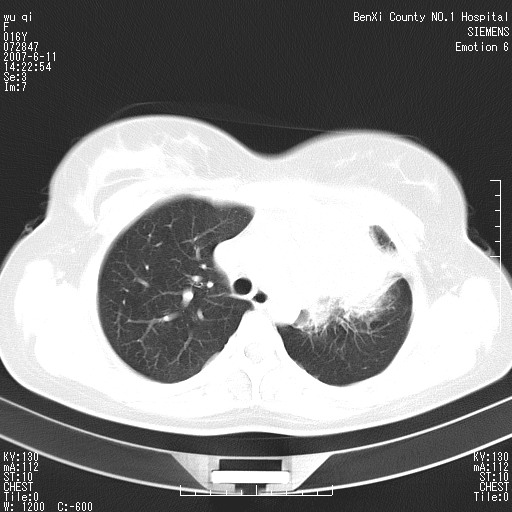

女.16、咳嗽、乏力、消受,食欲差,一个月余,无咯血,一个月前有发热。经抗炎治疗发热消失,仍咳嗽。平扫ct值34-45hu,增强后60-78hu明显强化,另外为了大家方便阅片,简单提下自己意见,纵隔内淋巴结肿大,左肺片影,其内密度不均,增强扫描明显强化,左肺上叶支气管可见支气管气象。尖段闭塞。冠状位可见左侧锁骨下静脉受压下移。请大家会诊,分析。

左上肺野纵隔旁软组织密度块影,增强欠均匀性强化,其内可见血管影穿梭,肿块周围之肺组织及纵隔气管均有不同程度受压改变;定位及定性均有困难...根据病史考虑以下几点:1.来源纵隔可能性较大,腺瘤?淋巴性肿瘤?其他?2.肺组织来源?左上肺占位(ca)?3.不排除原发性综合征可能?

左肺上叶支气管闭塞体积变小,纵隔内见淋巴结肿大,中心型肺癌左上叶肺不张可能大,建议做支气管镜检查,

肺不张会引起纵隔结构向患侧移位,而该病例纵隔是向右侧移位,且左侧锁骨下静脉受压移位,均提示病灶位于纵隔内。我感觉象是淋巴瘤,左肺病灶是因为阻塞性肺炎引起的。

其实这个病例平扫我和大家的诊断一样,考虑为肺结核,加上相似的症状。增强后我发现原来左侧的锁骨下静脉受压下移,

1。所以能不能就是肺外的病变呢?并且是实性的肿物。只有肺外的实性病变可以把锁骨下静脉压迫到如此地步?当然,结核可以粘联,可是谁见过结核如此可怕的牵拉作用,累及到肺外大血管了。

不知道大家为什么一口同声的赞同肺结核的诊断,有依据么?就算结核可及理解?那么支气管内膜结核怎么样解释,我并未见上叶主支气管有移行性狭窄。只能说上叶支气管受压下移,开口略向外。

在请问大家,左上叶支气管未见狭窄,顶多尖段闭塞,怎么会有如此大片的肺不张?就算是肺不张也顶多是一个小的尖段不张。再说请问大家看见代偿性气肿了么?

5。结核有强化可以理解,但是如此明显的强化,平扫ct值34-45hu,增强后60-78hu明显强化。局限于左肺的大片状病灶解释的通么?

定位: 综合影像我觉得起源于肺外。

定性: 1生殖源性肿瘤。

2胸腺瘤仍不能排除

3多组淋巴结肿大,淋巴瘤亦有可能。

4恶性神经原性肿瘤?

看过病例,肿块位于左侧胸膜顶和上纵隔,呈巨大不规则形软组织密度,边缘不清楚,和上纵隔诸结构不好分界,并可见肿大淋巴结影,左上叶支气管尚通畅,但上叶肺组织可见压迫性不张和膨胀不良。肿块内部可见一条明显的粗大血管影,经多层面追踪,应该是左侧锁骨下静脉。从以上表现来看,肿块的起源应该是在肺外,大致来源于胸膜顶部,向下、内生长。增强扫描,肿块内部可见多发血管分支,证明肿块血供较为丰富,从这一点上,比较符合间叶组织来源的恶性肿瘤,淋巴瘤往往表现为多发肿大淋巴团,但增强扫描内部出现迂曲血管的几率比较低,我觉得不是太象。间叶组织类别非常多,该类肿瘤只靠影像学很难鉴别,经皮穿刺活检不失为最好的方法,可以首先考虑。